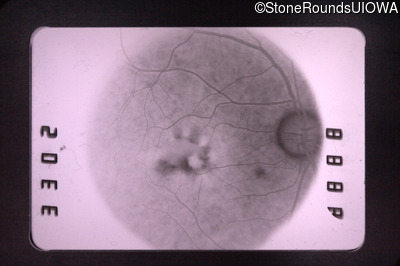

Fluorescein Angiography - Right - 20/30

Exemplar